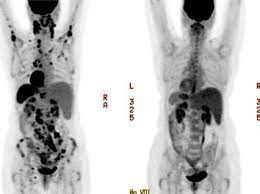

📌اللمفومة